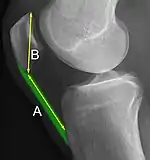

The Insall-Salvati ratio helps to indicate patella baja on lateral X-rays, and is calculated as the patellar tendon length divided by the patellar bone length. An Insall-Salvati ratio of < 0.8 indicates patella baja.[6]

- ↑ Yuranga Weerakkody and Frank Gaillard. "Patella baja". Radiopaedia. Retrieved 2018-01-16.

- 1 2 Douglas Dennis (2017-02-25). "TKA in Patella Baja (Infera)". Orthobullets. Retrieved 2019-02-08.